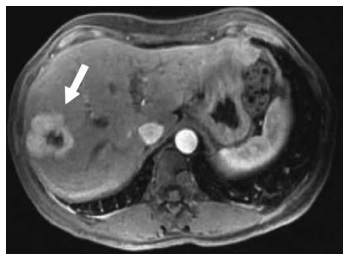

A lesão é definida como nódulo composto de hepatócitos de aparência normal e que ocorre em fígado com aspecto histológico normal. Ocorre predominantemente no sexo feminino (8:1) e em pacientes jovens. O tumor é geralmente assintomático e, nesses casos, não requer tratamento. É comumente um achado incidental em exames de imagem. Na US, possui um padrão inespecífico e é mal visualizada. É caracterizada com grande eficácia pela TC e pela RM, sendo possível a identificação da cicatriz central, que se apresenta com maior sinal que o restante da lesão. Tanto na RM como na TC quando essas características são presentes, a especificidade diagnóstica atinge 98%.

Assinale a alternativa que apresenta com qual lesão hepática benigna as características descritas e a imagem são compatíveis.